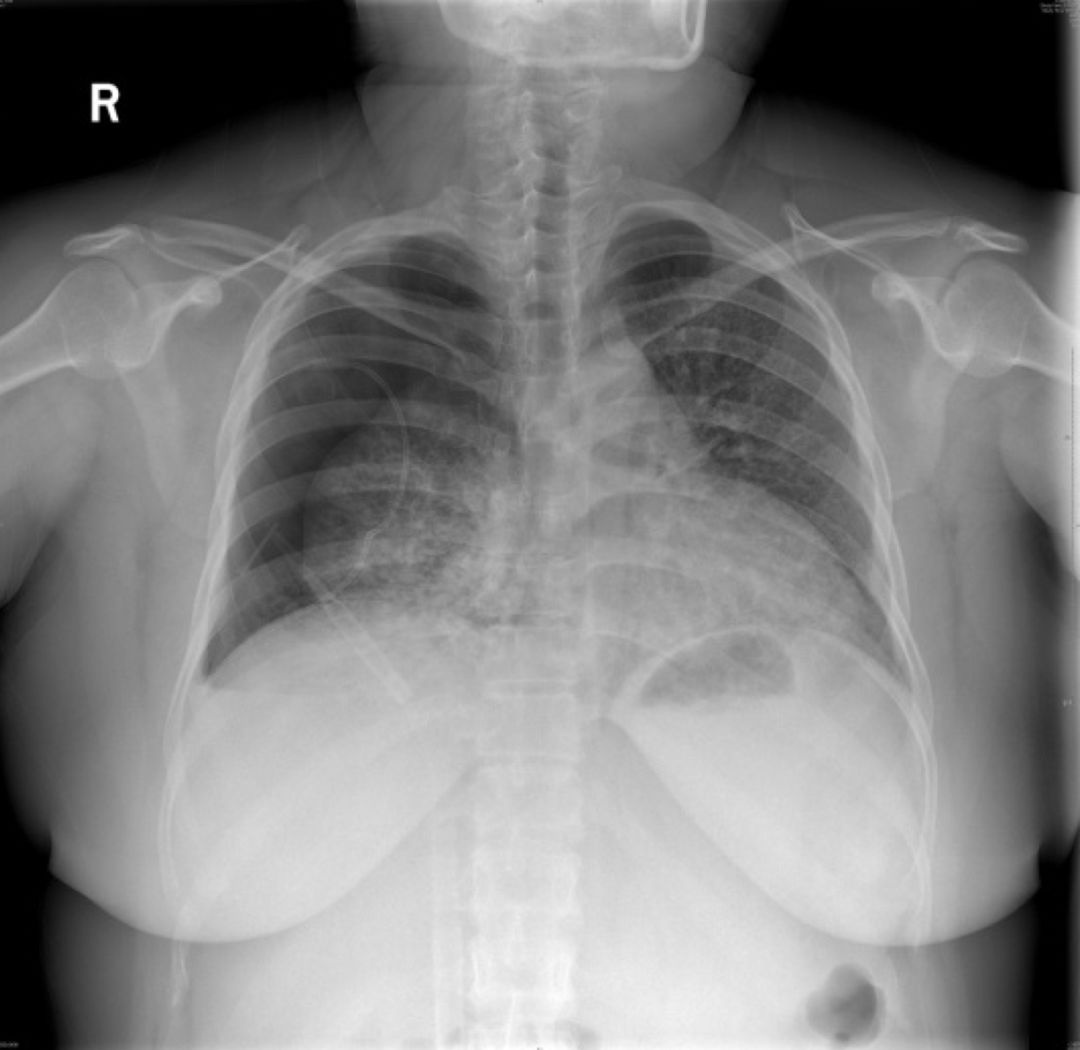

2019-5-13我院胸片

患者青年女性,因「咳嗽、咳痰、咯血半月余,胸痛8天」入院,急性起病,逐渐加重,胸部CT提示右侧气胸,双肺相对弥漫分布的气囊与结节,沿气管血管束分布,右下肺实变。肺部弥漫性囊泡样疾病,需要考虑肺淋巴管平滑肌瘤病(LAM)、BHD综合征、肺朗格汉斯组织细胞增生症(PLCH)、淋巴细胞性间质性肺炎(LIP)、感染性疾病如耶氏肺孢子菌肺炎(PCP)等疾病。LAM一般常见于育龄期女性,影像学以弥漫均匀分布的薄壁囊泡为主要表现,此例患者为年轻女性,肺部多发囊泡,需要考虑LAM,但囊泡不是薄壁,分布不均匀,形状不规则,不符合LAM的典型表现。PLCH一般多见于吸烟患者,影像学以奇形怪状的沿支气管血管束分布的囊泡样改变为特点,吸烟患者一般以上叶及中叶病变为主,不累及肋膈角,多系统病变患者可以累及肋膈角,本例需考虑PLCH可能。BHD综合征肺部表现为多发薄壁囊肿,形状不规则,多于基底部、外周、沿纵隔分布,其他系统表现可合并皮疹、肾肿瘤等,可有家族史,本例患者无BHD家族史,需进一步排查其他器官有无病变。LIP常有肺部多发囊泡改变,一般合并自身免疫性疾病,该患者需进一步完善自身抗体等风湿免疫相关指标,协助诊断。此外,还需考虑PCP、金葡菌感染等感染性疾病。PCP多见于免疫抑制宿主,可以有多发性肺气囊的表现,该患者无发热,无免疫抑制病史,目*考前**虑可能性不大。